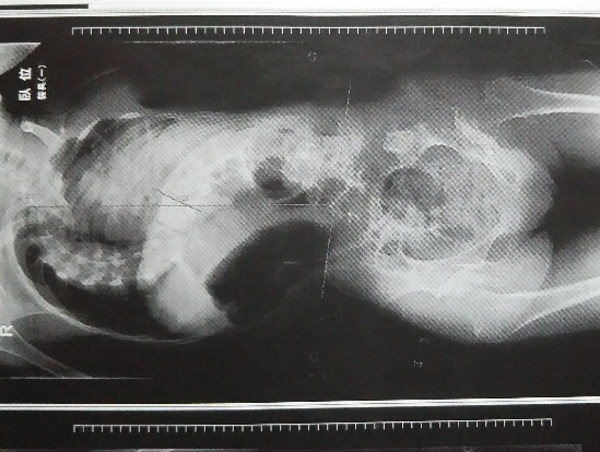

娘は中学校3年の時に腸閉塞の一種、腸回転異常症になり、10㎏体重が落ちて湾曲(脊椎の歪み)から回旋(脊椎のねじれ)の状態にまで悪化しました。

娘は腸閉塞の後、お腹を圧迫するコルセットを諦めました。硬くなった娘の背骨は、側弯症の手術をしても曲がったまま固定するしかなく、今の何とか歩ける状態がバランスを失って歩行できなくなる可能性があると言われ、手術も諦めました。

ねじれているので、ピントが合わず背骨全体が捉えるられません。

肩と骨盤の傾きの改善と、全体にピントが合ってねじれの改善が確認できました。